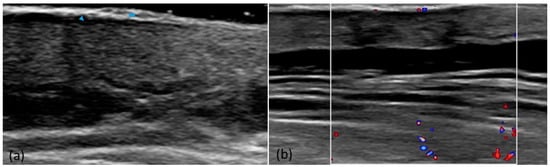

3.1. High-Frequency Ultrasound

4.1. Cutaneous Ultrasound

| Hyperechoic band | 60 (100%) |

| Hypoechoic band | 48 (80%) |

| Lack of damage to the subcutaneous tissue | 60 (100%) |

| Presence of vascularization | 28 (46.7%) |